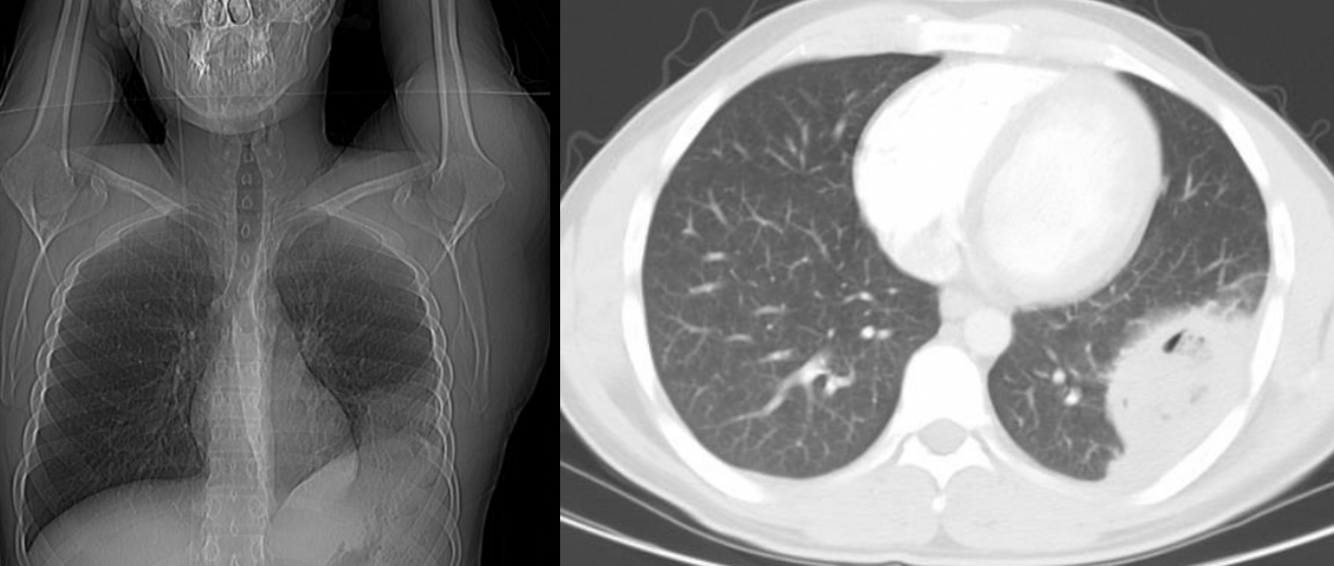

6

Q

Diagnóstico

A

TC contrastada